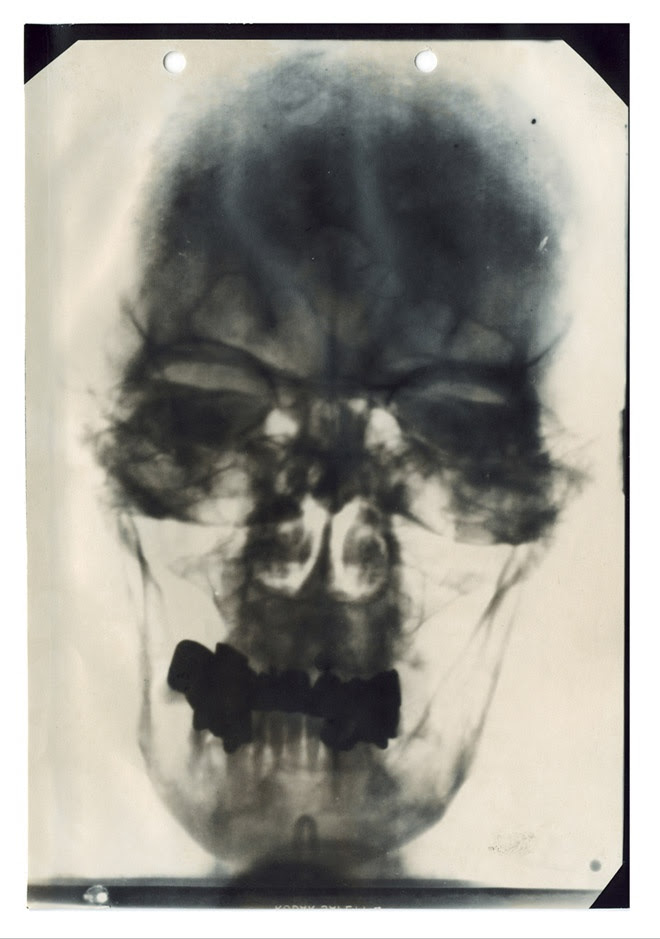

Miss America 1924Leather gloves worn by Lincoln to Ford's Theater on the night of his assassination. Blood stains are visible at the cuffs.Phoebe Mozee (aka: Annie Oakley). Famed for her marksmanship by 12 years old, she once shot the ashes off of Kaiser Wihelm II's cigarette at his invitation. When she outshot famed exhibition marksman Frank Butler, he fell in love with her and they married. They remained married the rest of their lives.This is one of five known X-rays of Hitler's head, part of his medical records compiled by American military intelligence after the German's surrendered and declassified in 1958. The records also include doctor's reports, diagrams of his teeth and nose and electrocardiograms. He had bad teeth, lots of fillings and crowns.Amy Johnson, English aviator 1903-1941 One of the first women to gain a pilot's licence, Johnson won fame when she flew solo from Britain to Australia in 1930. Her dangerous flight took 17 days. Later she flew solo to India and Japan and became the first woman to fly across the Atlantic East to West, she volunteered to fly for The Women's Auxiialry Air Force in WW2, but her plane was shot down over the River Thames and she was killed.Roald Amundsen was the first person to reach the South Pole. At approximately 3pm on December 14, 1911, Amundsen raised the flag of Norway at the South Pole and named the spot Polheim — “Pole Home.”The extraordinary life of Maud Allen: Seductive US dancing girl who was sued for being too lewd, outed as a lesbian, and fled London after being branded a German spy who was sleeping with the prime minister's wife.Caroline Otero, courtesan, the most sought after woman in all of Europe. She associated herself with the likes of Prince Albert I of Monaco, King Edward VII of the United Kingdom, Kings of Serbia, and Kings of Spain as well as Russian Grand Dukes Peter and Nicholas, the Duke of Westminster and writer Gabriele D’Annunzio. Six men reportedly committed suicide after their love affairs with Otero ended. Two men fought a duel over her. She was famed for her voluptuous breasts.Wedding day photograph of Abraham and Mary taken November 4, 1842 in Springfield, Illinois after three years of a stormy courtship and a broken engagement. Their love had endured.Washington, D.C., circa 1919. "Walter Reed Hospital flu ward." One of the very few images in Washington-area photo archives documenting the influenza contagion of 1918-1919, which killed over 500,000 Americans and tens of millions around the globe. Most victims succumbed to bacterial pneumonia following influenza virus infection.Mae Questel ca. 1930’s, the voice of Betty Boop and Olive Oyl, Minnie Mouse, Felix the Cat (for three shorts by the Van Beuren Studios), Little Lulu, Little Audrey and Casper, the Friendly GhostBea Arthur (née Bernice Frankel) (1922-2009) SSgt. USMC 1943-45 WW II. Enlisted and assigned as typist at Marine HQ in Wash DC, then air stations in VA and NC. Best remembered for her title role in the TV series “Maude” and as Dorothy in "Golden Girls".In 1911, Bobby Leach survived a plunge over Niagara Falls in a steel barrel. Fourteen years later, in New Zealand, he slipped on an orange peel and died.Emily Todd was Mary Todd Lincoln's half-sister. In 1856 she married Benjamin Helm, a Confederate general. After Helm's death in 1863 Emily Helm passed through Union Lines to visit her sister in the White House. This caused great consternation in the Northern newspapers. Emily Helm took an oath of loyalty to the Union and was granted amnestyMary Ellen Wilson (1864–1956) or sometimes Mary Ellen McCormack was an American whose case of child abuse led to the creation of the New York Society for the Prevention of Cruelty to Children. As an eight-year old, she was severely abused by her foster parents, Francis and Mary Connolly.Sacajawea. Stolen, held captive, sold, eventually reunited the Shoshone Indians. She was an interpreter and guide for Lewis and Clark in 1805-1806 with her husband Toussaint Charbonneau. She navigated carrying her son, Jean Baptiste, on her back. She traveled thousands of miles from the Dakotas the Pacific Ocean. The explorers, said she was cheerful, never complained, and proved to be invaluable. She served as an advisor, caretaker, and is legendary for her perseverance and resourcefulness.A Confederate and Union soldier shake hands during a celebration at Gettysburg in 1913. Image from the Library of Congress. July 1-3, 2013 marks the 150th Anniversary of the Battle of Gettysburg.Sergeant Stubby (1916 or 1917 – April 4, 1926), was the most decorated war dog of World War I and the only dog to be promoted to sergeant through combat. America's first war dog, Stubby, served 18 months 'over there' and participated in seventeen battles on the Western Front. He saved his regiment from surprise mustard gas attacks, found and comforted the wounded, and even once caught a German spy by the seat of his pants (holding him there til American Soldiers found him).Nightwitches - Female Russian bombers who bombed Germany during WW2. They had old, noisy planes & the engines used to conk out halfway through their missions, so they had to climb out on the wings mid-flight to restart the props. To stop Germans from hearing them & starting up the anti aircraft guns, they’d climb to a certain height, coast down to German positions, drop their bombs, restart their engines in midair & get the hell out of dodge. Their leader flew 200+ missions & was never captured.Chief Petty Officer Graham Jackson plays “Going Home” as FDR’s body is borne past in Warm Springs, GA, where the President was scheduled to attend a barbecue on the day he died. April, 1945.